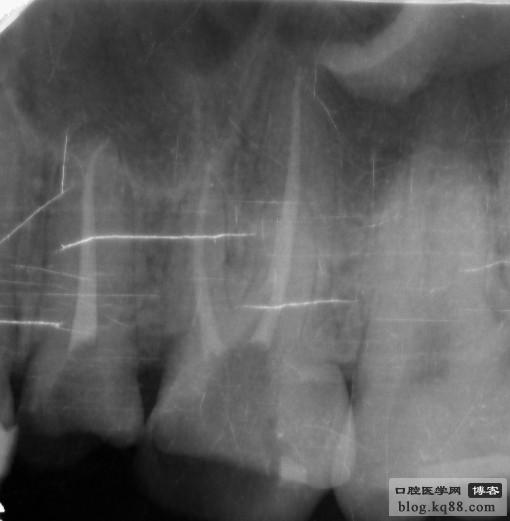

上頜是保留殘根覆蓋義齒,下頜是種植修復(fù),仔細(xì)看左上3側(cè)支根管被根充

左下5側(cè)支根管被根充